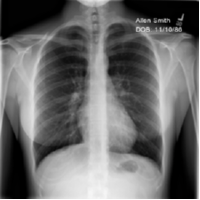

We simulate eight clients using different numbers of training images and local batch sizes in a cross-silo FL scenario with horizontal data partitioning for a chest X-ray image classification task. Each client trains an ImageNet-pretrained [42] ResNet-18 [21] for one epoch per round using a stochastic gradient descent (SGD) optimizer without momentum and a step-wise learning rate decay by a factor of 0.1 at every 40 rounds before sending model updates to the server for a total of 100 rounds. We study the gradient inversion attacks in both gray-scale and color image classification applications using two datasets, A and B. Dataset A consists of publicly available chest X-ray images from normal patients and patients who tested positive for COVID-19 [43, 44]. As input prior, we compute a mean image from a different publicly available dataset, namely the ChestX-ray14 dataset [45]. Dataset B consists of publicly available color fundus images from the Rotterdam EyePACS AIROGS train set [46]. The input prior for experiments using dataset B was generated by computing the mean image over images available through the ODIR-2019 challenge. The data used for training, validation, and testing data for both datasets is available online111 Dataset A (Chest X-ray): FL data prior data; Dataset B (Fundus color images): FL data prior data . Table II shows a summary of the local training batch size and number of training images that were used for each client. Each client has its own validation set of 200 cases that will be used to select the best global model based on the average validation accuracy. The selected global model is finally evaluated on the testing set. Except for client 9, each client training set contains the same number of normal and COVID-positive cases in order to simulate clients with balanced class distributions. Client 9 shares its only training image (a normal case) and its validation set with client 1. As a result, client 9 is at the highest risk of data leakage as it is sending model updates based on a single image and a batch size of one and will be referred to as the “high-risk client”. We intentionally utilize relatively small batch sizes in order to study the effect of our new inversion attack on clients with varying amounts of training data (and therefore, local training iterations)222All experiments are using Clara Train SDK 4.0 for local model training and evaluation. NVIDIA FLARE [47] is used to record model updates in a simulated FL setting. The inversion software is implemented in PyTorch and available at https://github.com/NVlabs/DeepInversion. We use a PyTorch version of tf.privacy.DPGradientDescentGaussianOptimizer to implement DP-SGD.. Therefore, all clients investigated in this study could be considered of higher risk than in real-world FL scenarios where clients use larger amounts of training data and batch sizes (see also the discussion in Section IV).